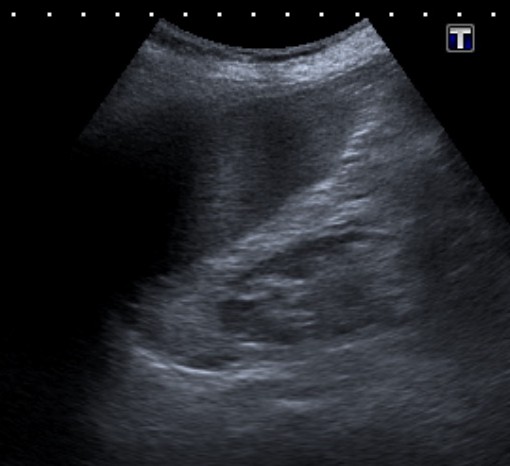

3- Ecografía:

No indicada sistemáticamente.

Tiene varias ventajas, es una prueba con bajo riesgo, barata, disponible, sin radiación y no requiere el uso de material de contraste. Suele ser la primera prueba que se realiza para valorar una pielonefritis. Sin embargo, en adultos es una herramienta que no caracteriza bien la infección renal, por ello, la mayoría de pacientes tienen un resultado negativo, pudiendo demostrar signos en tan solo un 24% de casos y por ello que decimos que infraestima la gravedad de la pielonefritis. Con el uso de material de contraste ecográfico (microburbujas) la S y E de la ecografría es mayor, sin embargo, son necesarios más estudios al respecto.

Cuando se dan hallazgos, lo más frecuente es observar un aumento del tamaño renal, hidronefrosis, litiasis o alteraciones de la vía urinaria. Otros signos que a veces pueden observarse incluyen colecciones, pérdida de definición del seno renal por el edema, focos hipoecoicos por edema o colecciones, focos hiperecoicos de hemorragía, pérdida de diferenciación córtico-medular, áreas hipoperfundidas con baja señal Power Doppler. Las calcificaciones pueden ser difíciles de distinguir del gas. Puede ser limitada para detectar focos de infección perirrenal o abscesos pequeños en infecciones en fases precoces.